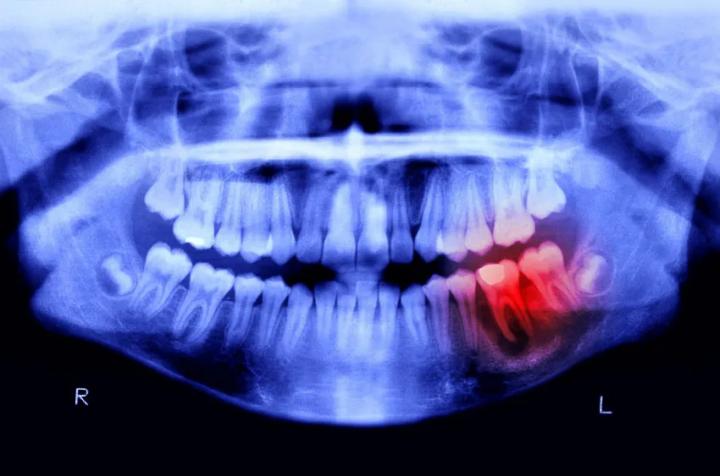

CientÃficos crean un fármaco para regenerar dientes perdidos

En un avance revolucionario en el campo de la medicina dental.